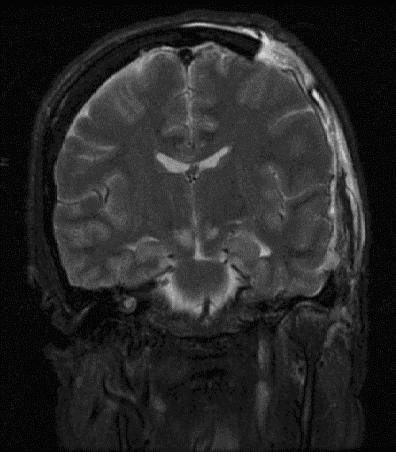

頭部CT:最も重要な検査であり、血腫の場所、大きさ、形状などを確認する。

MRI:頭部CTよりも詳細な画像が得るために行う。